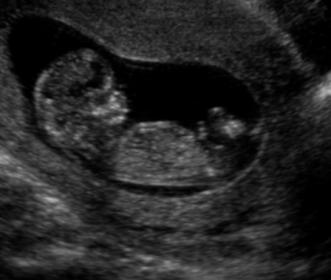

Hi everyone! Here are some scans from my 12w,4d U/S. I'm new to this. Any guesses? :)

Attachment 7013